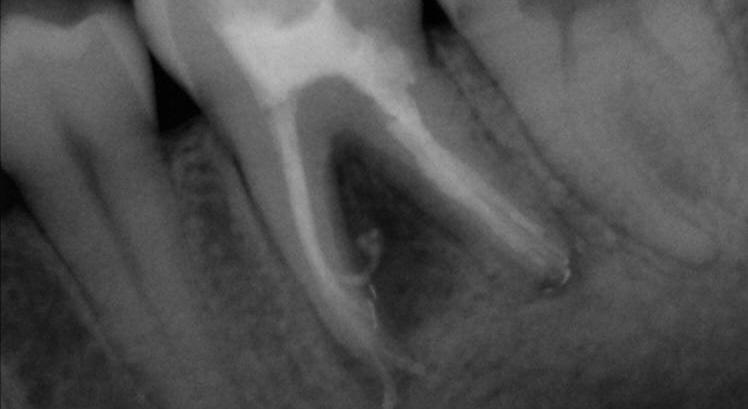

Case 2: A 52-year-old female referred to the clinic for the treatment of tooth 21. Intra-oral examination showed a poor restoration on tooth 21. Percussion and palpation were negative with mobility grade 1. Radiographic examination showed an unsatisfactory restauration on tooth 21 with an apical radiolucency. After obtaining the written consent, the treatment was carried out. The area was anesthetized. Tooth was isolated using the rubber dam and access cavity was opened.

The root canal used for shaping was the EdgeTaper Blaze Utopia to size F2 #25. The final irrigation protocol was performed by a continuous delivery of EDTA and NaOCl. Solutions were activated using ultrasonic activation - 1 minute per solution. Canals were dried and obturated using hydraulic condensation with EdgeBioCeramic Sealer (EdgeEndo).

Lateral and secondary canals are visible on the post operative radiograph.